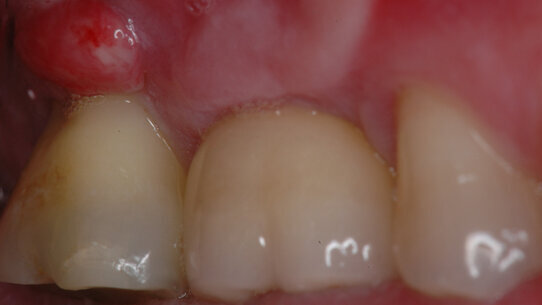

Il paziente di anni 46 si presenta con difficoltà alla masticazione sul lato destro. All’esame clinico si evidenzia un rigonfiamento ascessuale nell’area vestibolare del secondo molare superiore (Fig. 1) con sondaggio di 2° grado della forcazione e mobilità di grado 1.

La visita di controllo effettuata dopo una settimana permette di osservare la normalizzazione della zona vestibolare del 17, la scomparsa del sondaggio di 2° grado della forcazione vestibolare e l’assenza di mobilità, dati che confermano l’origine endodontica dell’infezione (Fig. 5).